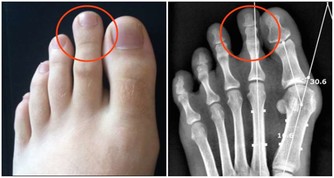

喝酒其實會帶給身體很多不同的負擔,像說高血壓跟增加心臟疾病的可能性。